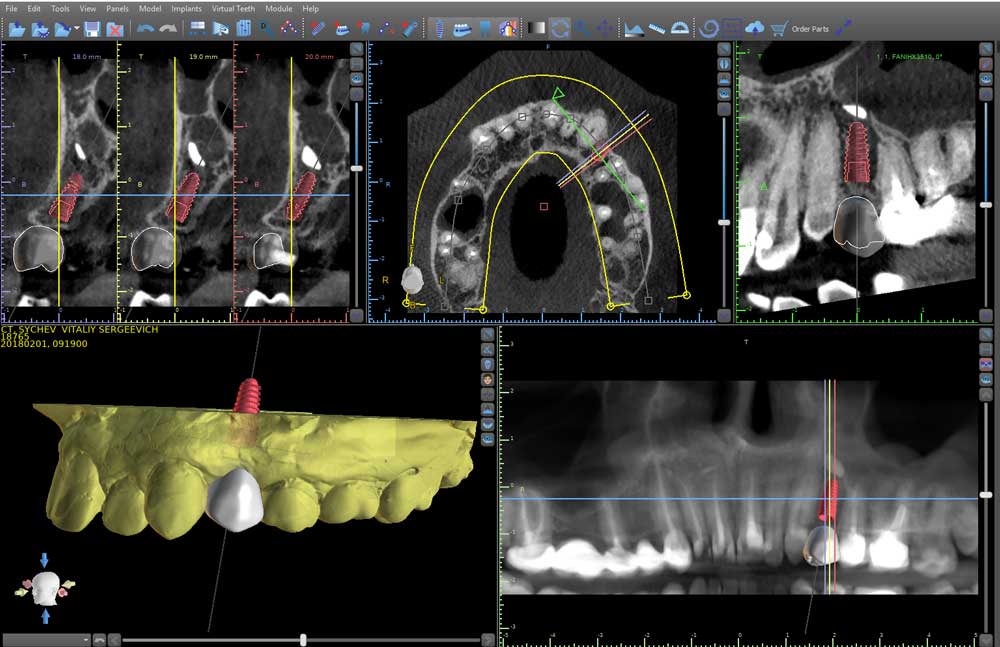

В программе-планировщике мы выбираем размеры имплантатов, расставляем их на виртуальной модели челюсти пациента в безопасном положении, учитывая расположение крупных нервов, гайморовых пазух и других важных анатомических образований. По этим данным программа создают точный хирургический шаблон, в котором заложена вся информация о положении имплантатов: глубина и углы наклона, именно те, которые врач спланировал в программе. На планирование хирургического шаблона требуется всего лишь 1 рабочий день.